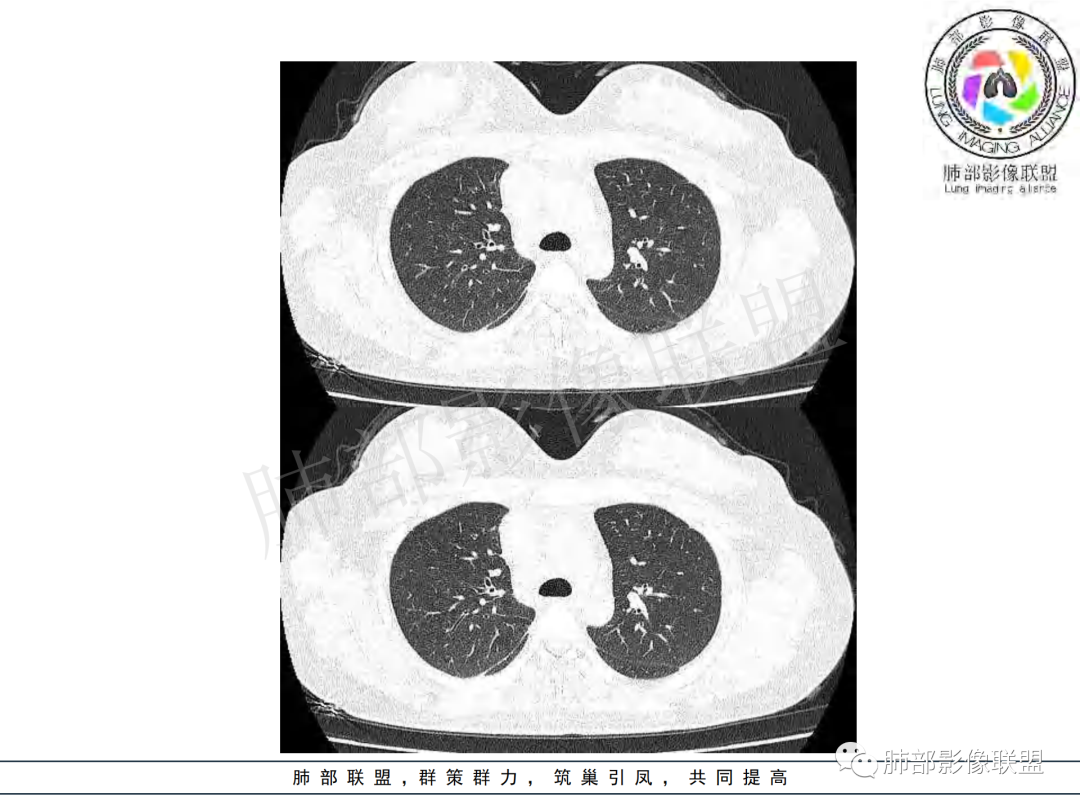

女,20,病程长达8月,发热、胸痛、右侧胸腔积液病史。胸部CT:右肺门旁不规则肿块影,右中间支气管腔内结节,纵隔多发淋巴结肿大;强化不均匀,灶性坏死灶,环形强化;右侧少量胸腔积液并局部肉芽肿样突起。年轻女性,长病程,多部位,考虑慢性炎症,结核?鉴别肿瘤。

年轻女性,慢性病程,发热、胸痛。右肺门旁不规则肿块影,纵隔多发淋巴结肿大;强化不均匀,环形强化;右侧少量胸腔积液;首先考虑结核,鉴别肿瘤,结节病。

慢性病程,前纵隔右肺门旁多发淋巴结肿大;强化不均匀,环形强化;右侧少量胸腔积液;考虑结核,鉴别结节病。

青年女性,发热、胸痛、右侧胸腔积液病史,病程8个月。曾多次抗炎后均有好转。CT:右肺门旁肿块影,双侧胸膜结节,纵隔多发淋巴结肿大,边缘模糊;增强渐进性明显强化,纵膈淋巴结较彻底坏死灶,边缘环形强化。考虑结核,鉴别恶性肿瘤。

本例患者,年轻女性,慢性病程,多次抗感染治疗效果不佳,实验室检查示白细胞及中性粒细胞不高,不支持普通细菌感染,虽然肺泡灌洗液X-Pert检测阴性,结合患者胸部CT结核感染亦不能排除,胸部CT主要表现为右侧肺门及纵隔淋巴结肿大,仔细观察不难发现右中间支气管内新生物凸向管腔内,增强扫描,右肺门(10R)及纵隔淋巴结(2R,4R)明显不均匀强化,内部呈不规则低密度无强化区,被周边高强化区包绕(环形强化)的特点,首先应当想到纵隔淋巴结结核诊断。淋巴结分布亦不符合肺部恶性肿瘤迁徙途径。